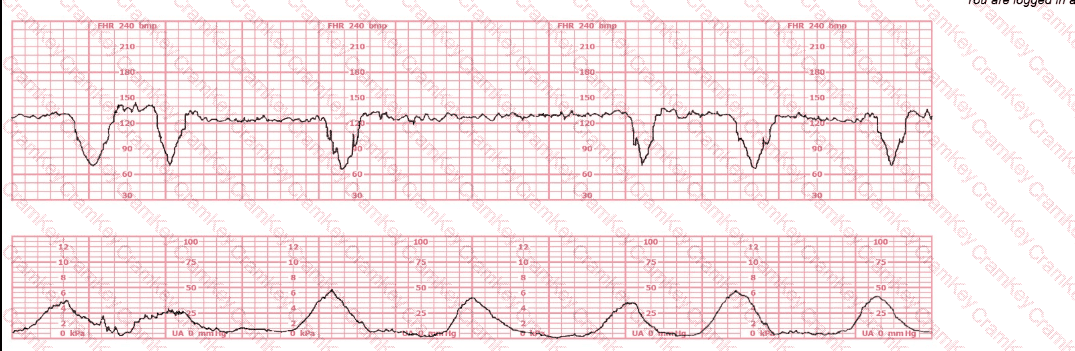

A woman is being induced with oxytocin. The tracing shown is representative of 20 minutes. Based on this tracing, the next step would be to:

Questions 9

Options:

A.

Discontinue oxytocin

B.

Place a spiral electrode

C.

Proceed to operative birth

Discussion